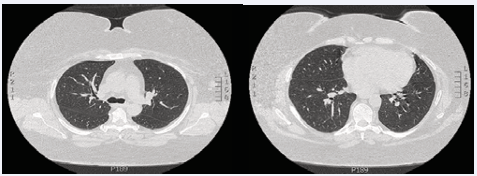

Figure 2 CT Non-Contrast 4 weeks after stopping extended-release Exenatide and starting prednisone, showing complete resolution of bilateral ground-glass.

A diagnosis of acute eosinophilic pneumonia was made and the patient was started on high dose prednisone (0.5mg/kg). Within 48 hours the patient’s symptoms markedly improved as well as her hypoxemia, and she was discharged home with supplemental oxygen at 2 liters per minute. At one week followup all symptoms had resolved and the patient was not requiring supplemental oxygen. Repeat non-contrast chest CT at four weeks showed complete resolution of the bilateral ground-glass airspace opacities. All laboratory data revealed no evidence of a rheumatologic or infectious etiology and thus, the patient was ultimately diagnosed with acute eosinophilic pneumonia due to extended-release Exenatide.